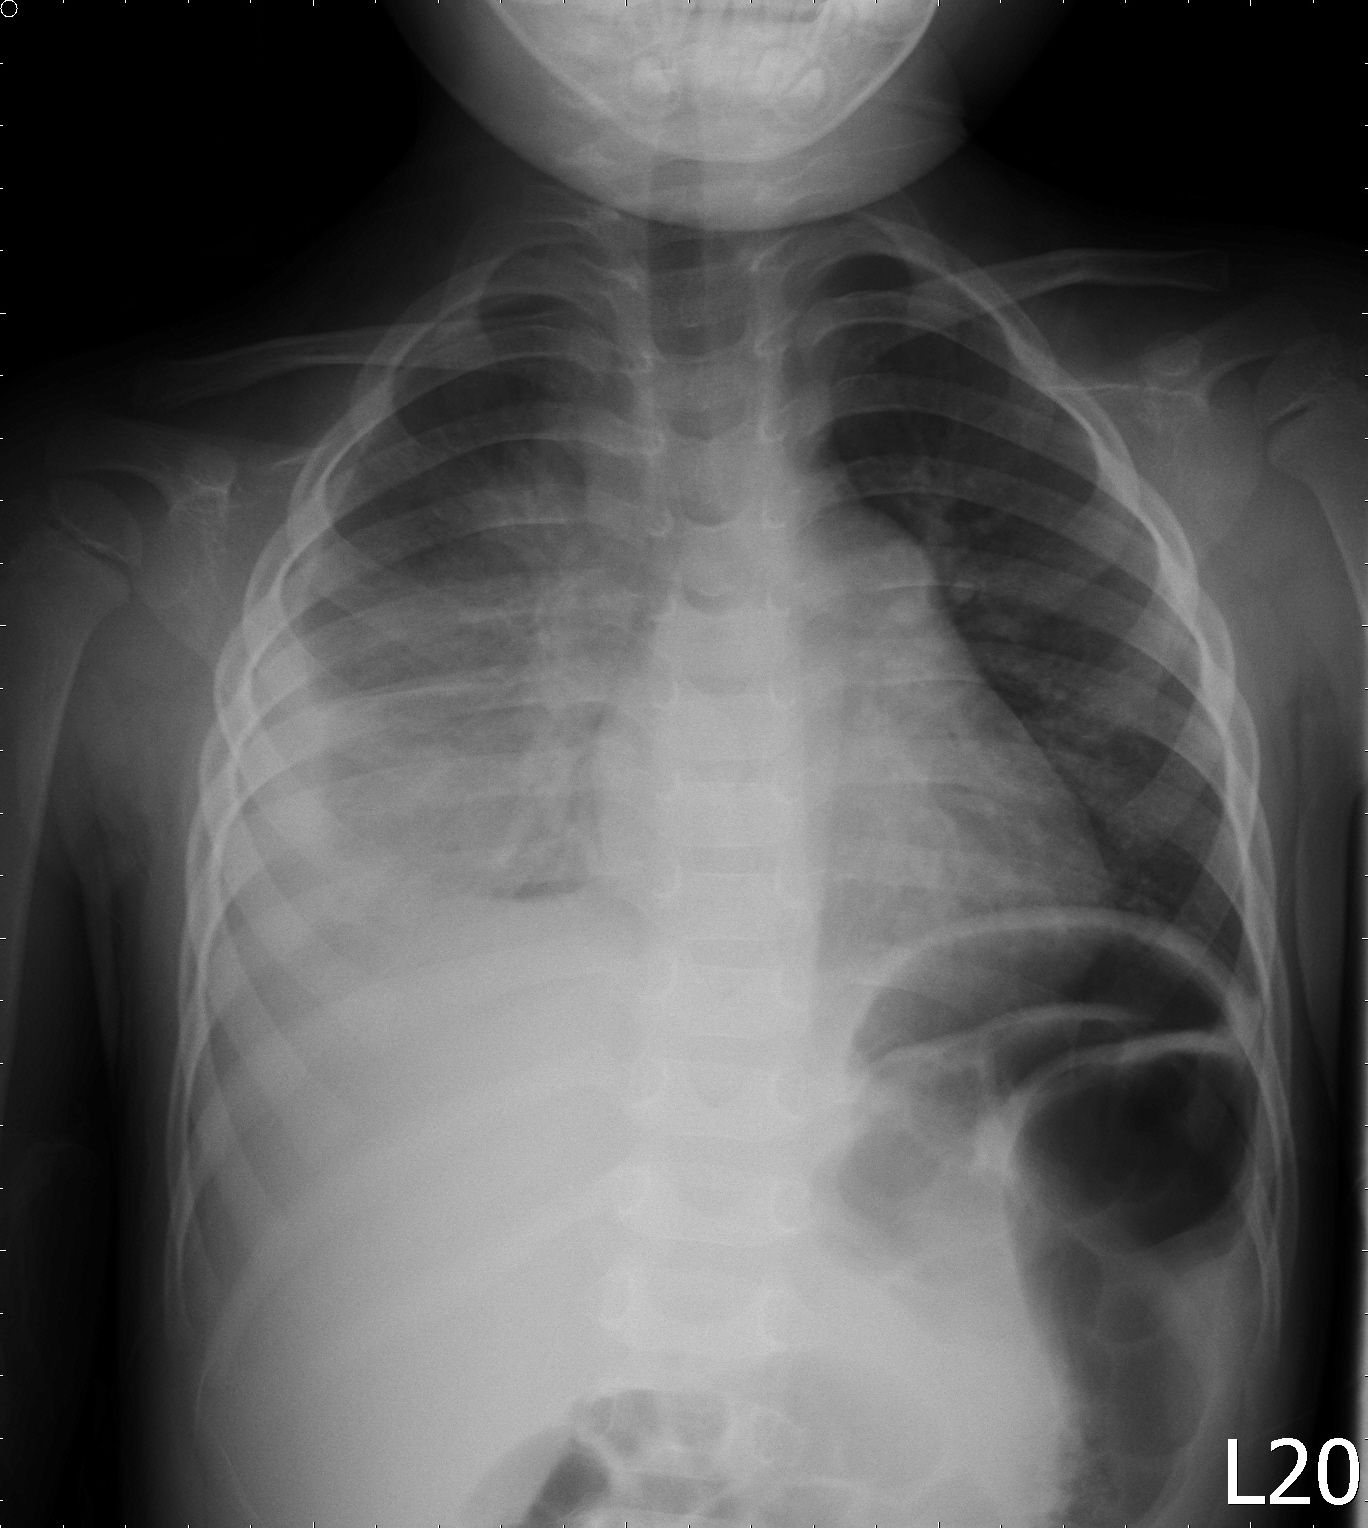

以下就是他一直說"我沒事"的相片

是大葉高島屋肺炎耶! 驗血結果也顯示出驚人的...異常

如果當天沒積極處理又被退貨, 後果實在是不敢想像